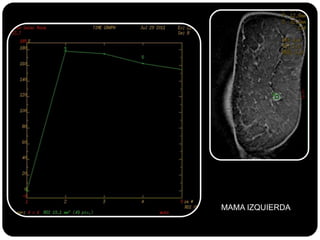

Paciente femenina de 66 años con historia clínica de 1er gesta antes de los 30 años y antecedentes de lactancia positiva, presenta una lesión palpable en la mama derecha. Los estudios radiológicos indican un diagnóstico de bi-rads 5, con biopsias revelando adenocarcinoma lobulillar infiltrante en la glándula mamaria derecha y adenocarcinoma ductal in situ en la izquierda. El caso fue evaluado por las doctoras Jacqueline Preciado Vargas y Beatriz E. González Ulloa.